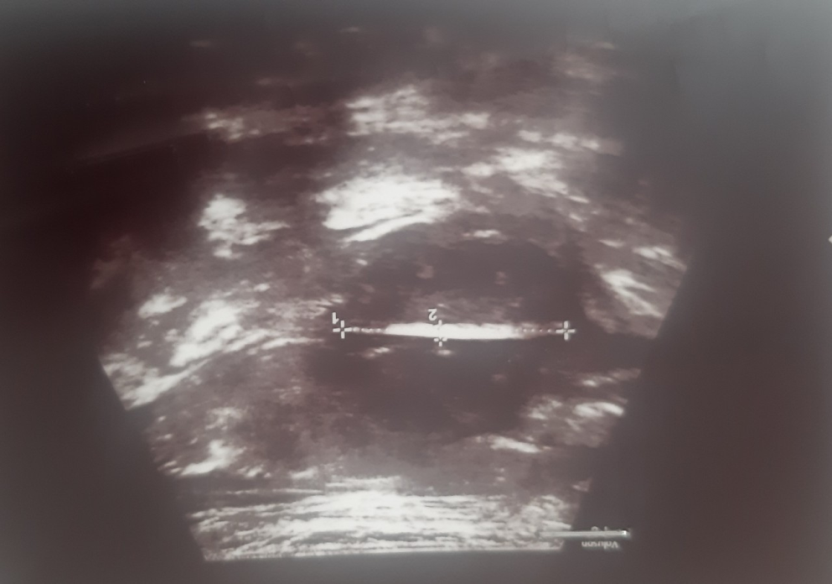

Theo y văn, phần lớn dị vật đi qua đường tiêu hóa ra ngoài một cách an toàn trong vòng 1 tuần. Tuy nhiên, khoảng 1% các dị vật sắc nhọn như kim, lưỡi lam, tăm xỉa răng, xương gà, xương thỏ và xương cá có thể xuyên qua thành ruột và thường gây viêm phúc mạc đòi hỏi phải mổ cấp cứu.Tuy nhiên trong trường hợp này sau khi xương chui qua thành ruột, di cư vào ổ phúc mạc thì lỗ thủng thành ruột gây ra do quá trong di cư này tự bít lại. Dị vật được mạc nối lớn bao bọc tạo ổ áp xe như hình ảnh siêu âm dưới đây

Hình ảnh mảnh xương cá trong ổ phúc mạc bệnh nhân qua siêu âm